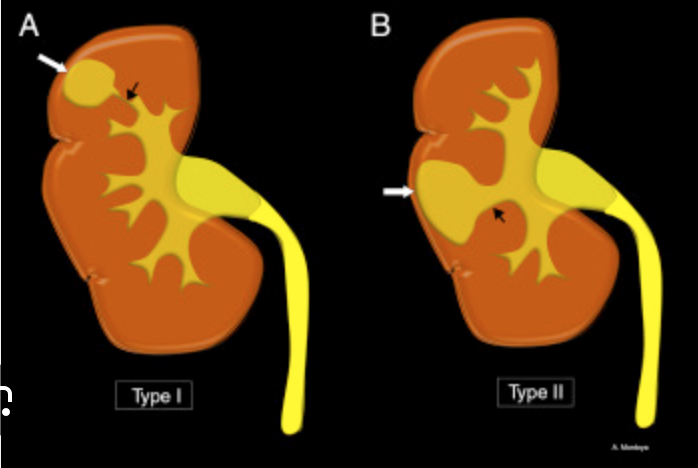

Posterior Urethral Valves

• Keyhole appearance

• Due to dilatation of the bladder and posterior urethra

• The bladder will typically have irregular contour due to chronic outlet obstruction - all because th ebladder is contracting against a closed door

• Elongated

• Trabeculated

• Maybe some diverticula